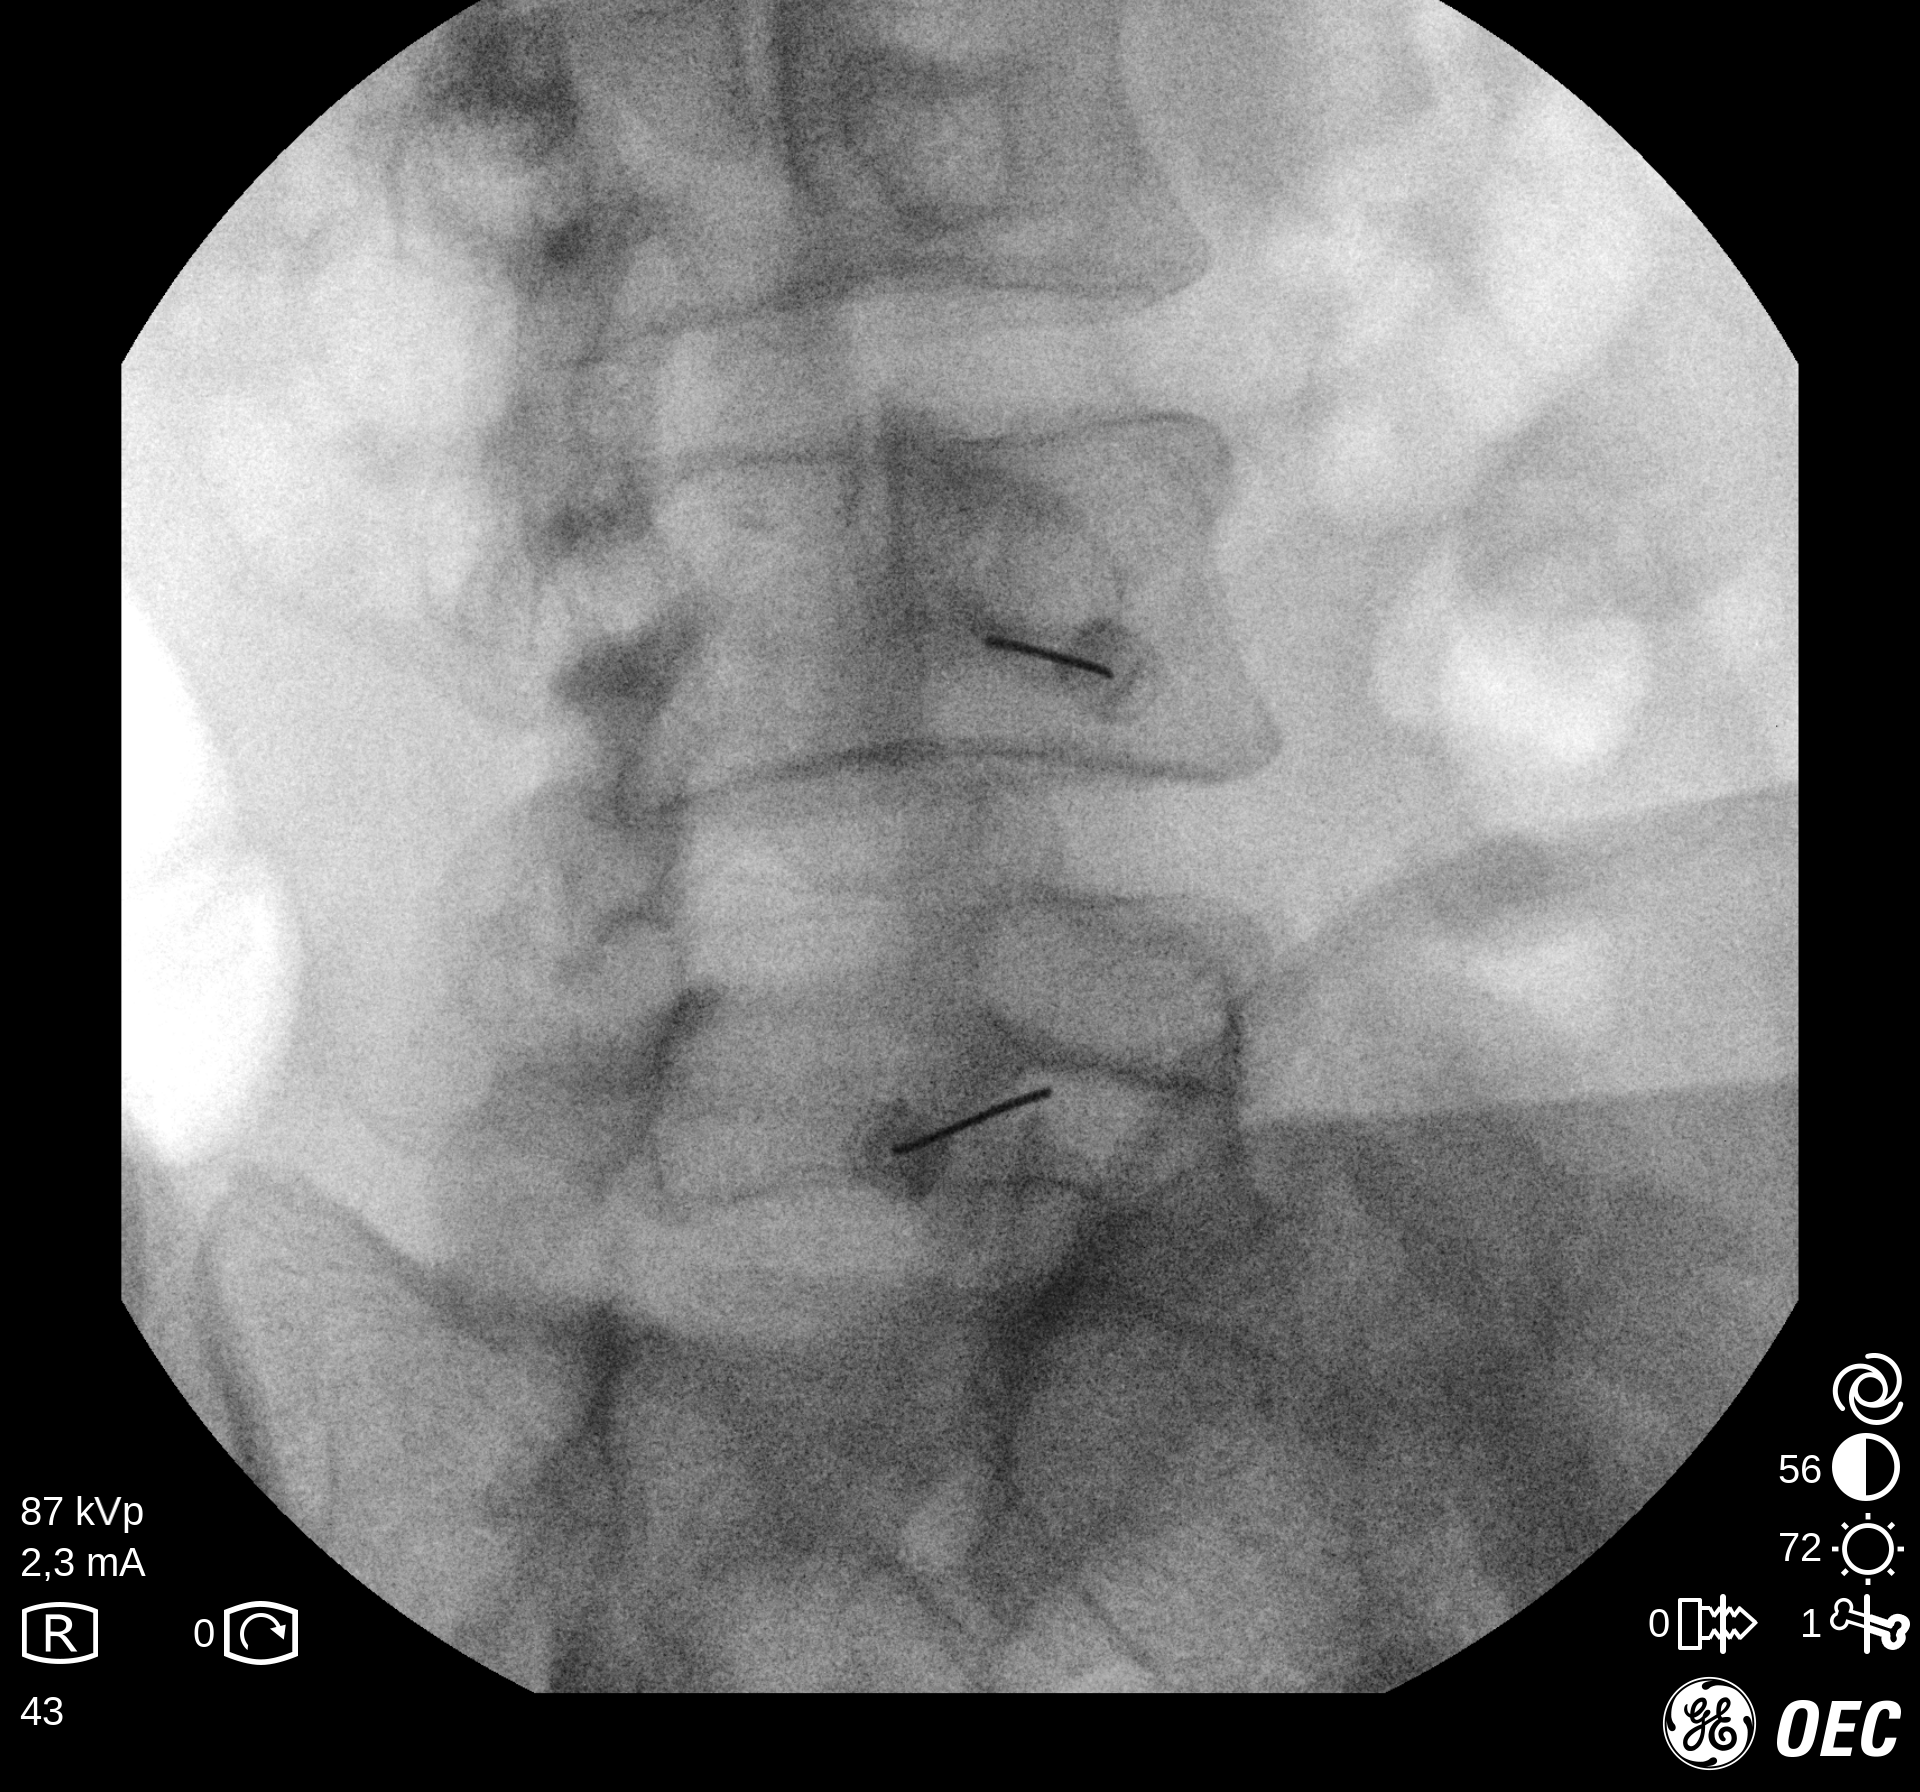

Ασθενής με σπονδυλαρθρίτιδα και 2 δισκοκήλες

Ασθενής 86 ετών με έντονο άλγος οσφύος, αντανάκλαση στο κάτω άκρο και αιμωδίες αριστερού άκρου ποδός απο 2μήνου λόγω σπονδυλαρθρίτιδας και 2 δισκοκηλών σε 2 επίπεδα. Με τοπική αναισθησία τοποθέτηση 2 βελόνων.  Έλεγχος σωστής τοποθέτησης με χρήση σκιαστικού και εισαγωγή μείγματος αναλγητικών. Άμεση ανακούφιση με αποτέλεσμα που διατηρείται 1.5 χρόνο μετά.